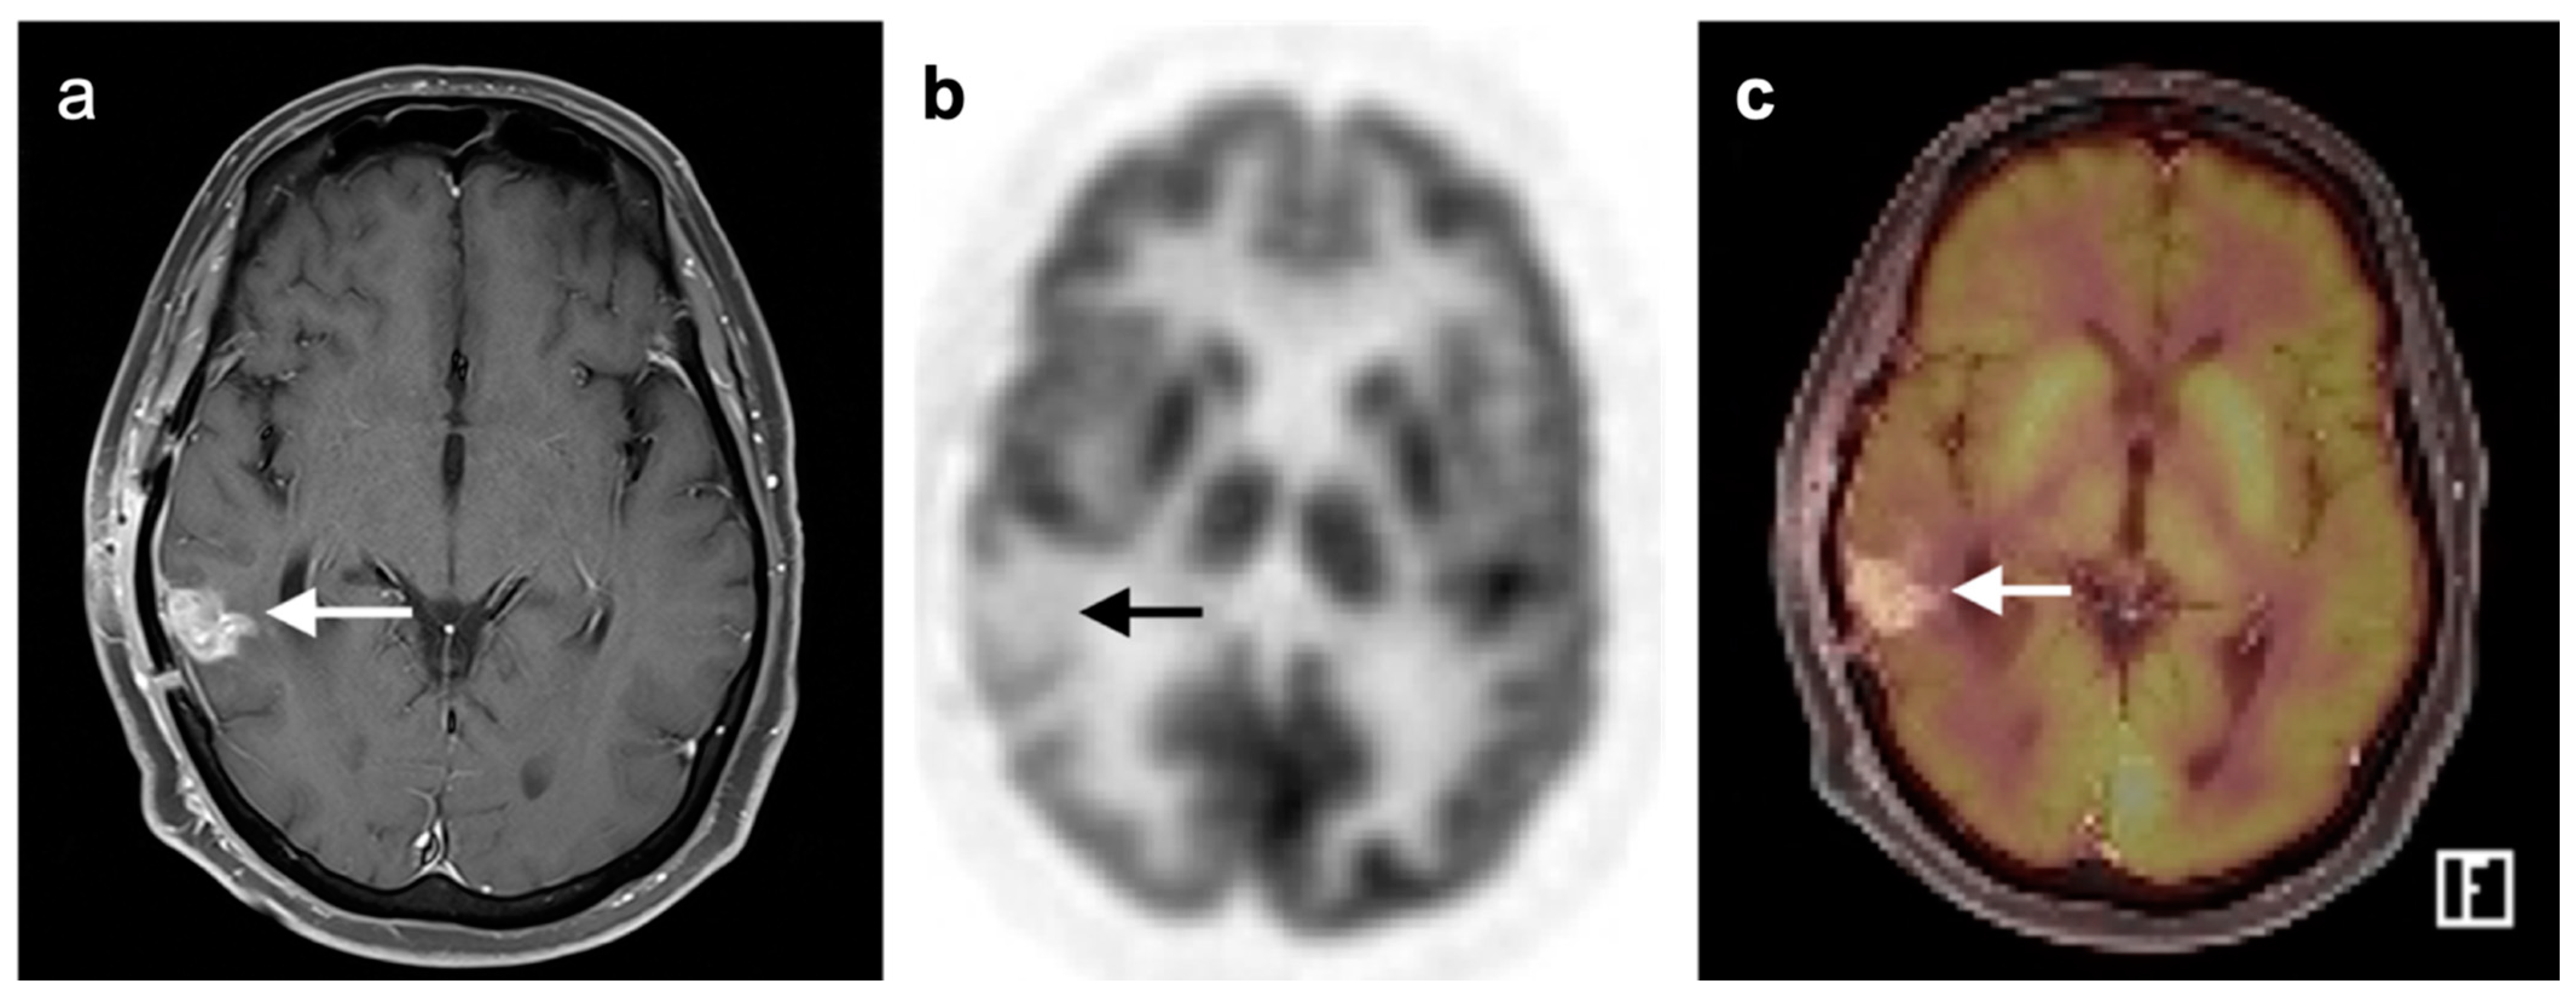

3.4. CNS Lymphoma

3.5. Brain Metastases

3.6. Response to Therapy